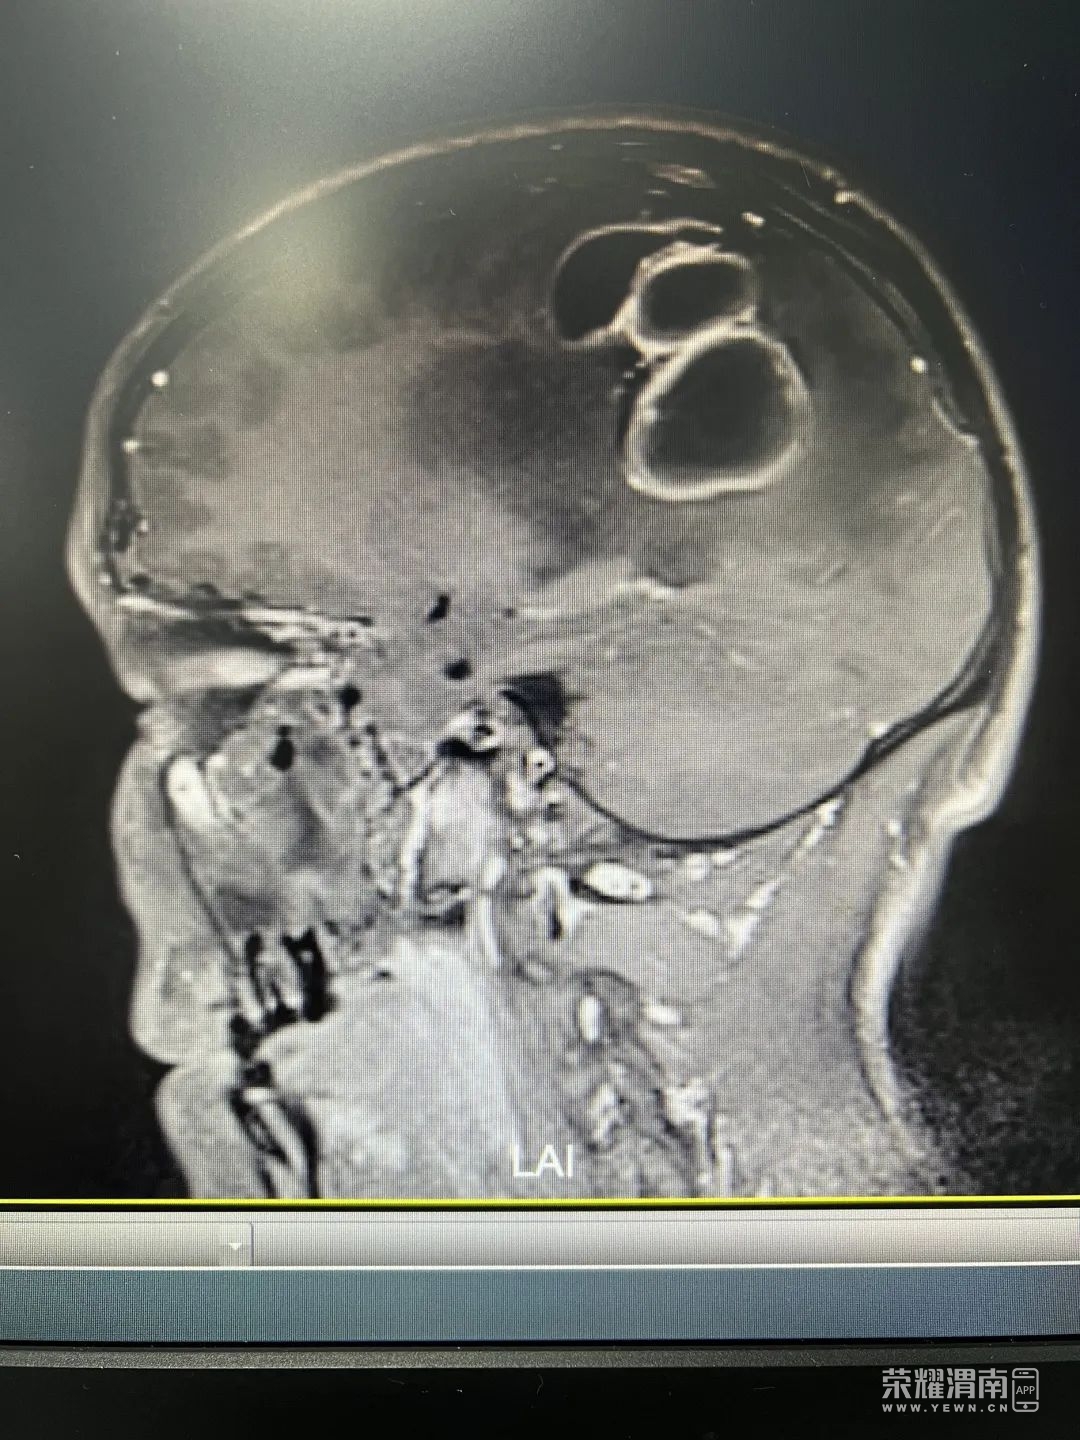

张眉了解了病史后,立即为小刘安排查体,发现他右上肢肌力只有Ⅱ级,而且有轻度面瘫现象迅速联系CT室为其做了头颅CT检查显示:“左侧顶枕叶异常密度影,伴周围脑水肿,脑中线右偏,建议MR(磁共振)平扫及增强检查”。张眉立马安排小刘住院治疗。

张眉耐心解释说,为小刘采取的手术治疗并非传统的开颅手术,考虑到脑脓肿为多囊性,可以通过高科技手段将脓肿形态进行三维重建,精准定位病变位置,在CT引导下,穿刺一根细管进入脓肿腔将脓液吸出。这种手术切口很小,一般3cm左右,可以避免对脑部周边的脑组织损伤,而且可以将脓肿清除地更彻底,手术费用相对来说也便宜不少。

经过神经外科团队共同讨论病情并制定详细的手术方案,完成必要的术前准备后,小刘被推进了手术室。手术过程很顺利,通过术前CT立体定向技术精准定位脓腔位置后,术中通过钻颅穿刺置入引流管抽吸出55ml脓性乳白色液体,立即将脓液进行病原学送检,同时术中充分冲洗脓肿腔,一个小时左右手术就结束了。